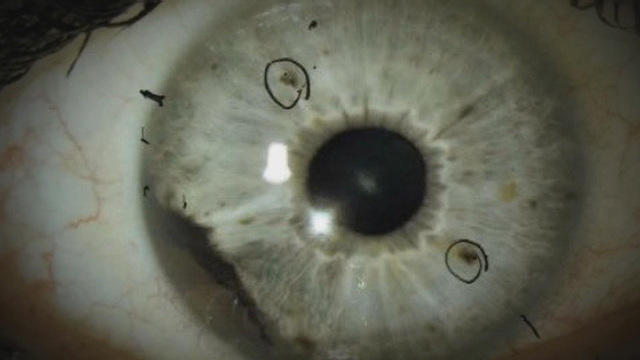

The melanoma, a type of cancer that develops in melanin – the pigment that gives skin its colour, only occurs in about six out of one million people but at least 18 people have been diagnosed with ocular melanoma recently – curiously all have ties to one or both of the communities in Huntersville, North Carolina or Auburn, Alabama.

The foundation also said this type of melanoma is rarer than skin cancer. Risk factors include fair skin, light coloured eyes, or over-exposure to UV light. The median age of patients is 55, however, the women in Alabama were diagnosed between the ages of 27 to 31.